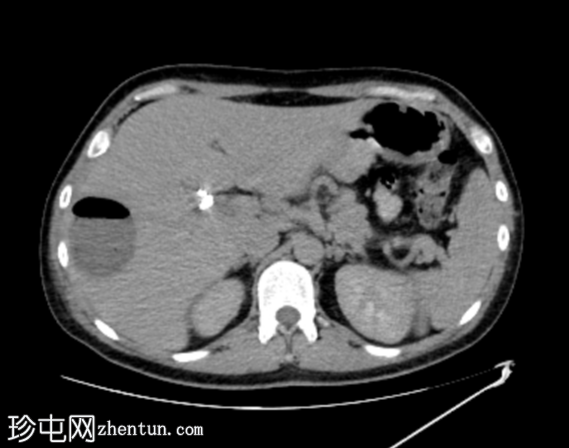

定位扫描

轴位

平扫图像显示胆囊切除夹、胆道积气、胆总管支架及右肝叶VIII段囊性病变伴气液平面。